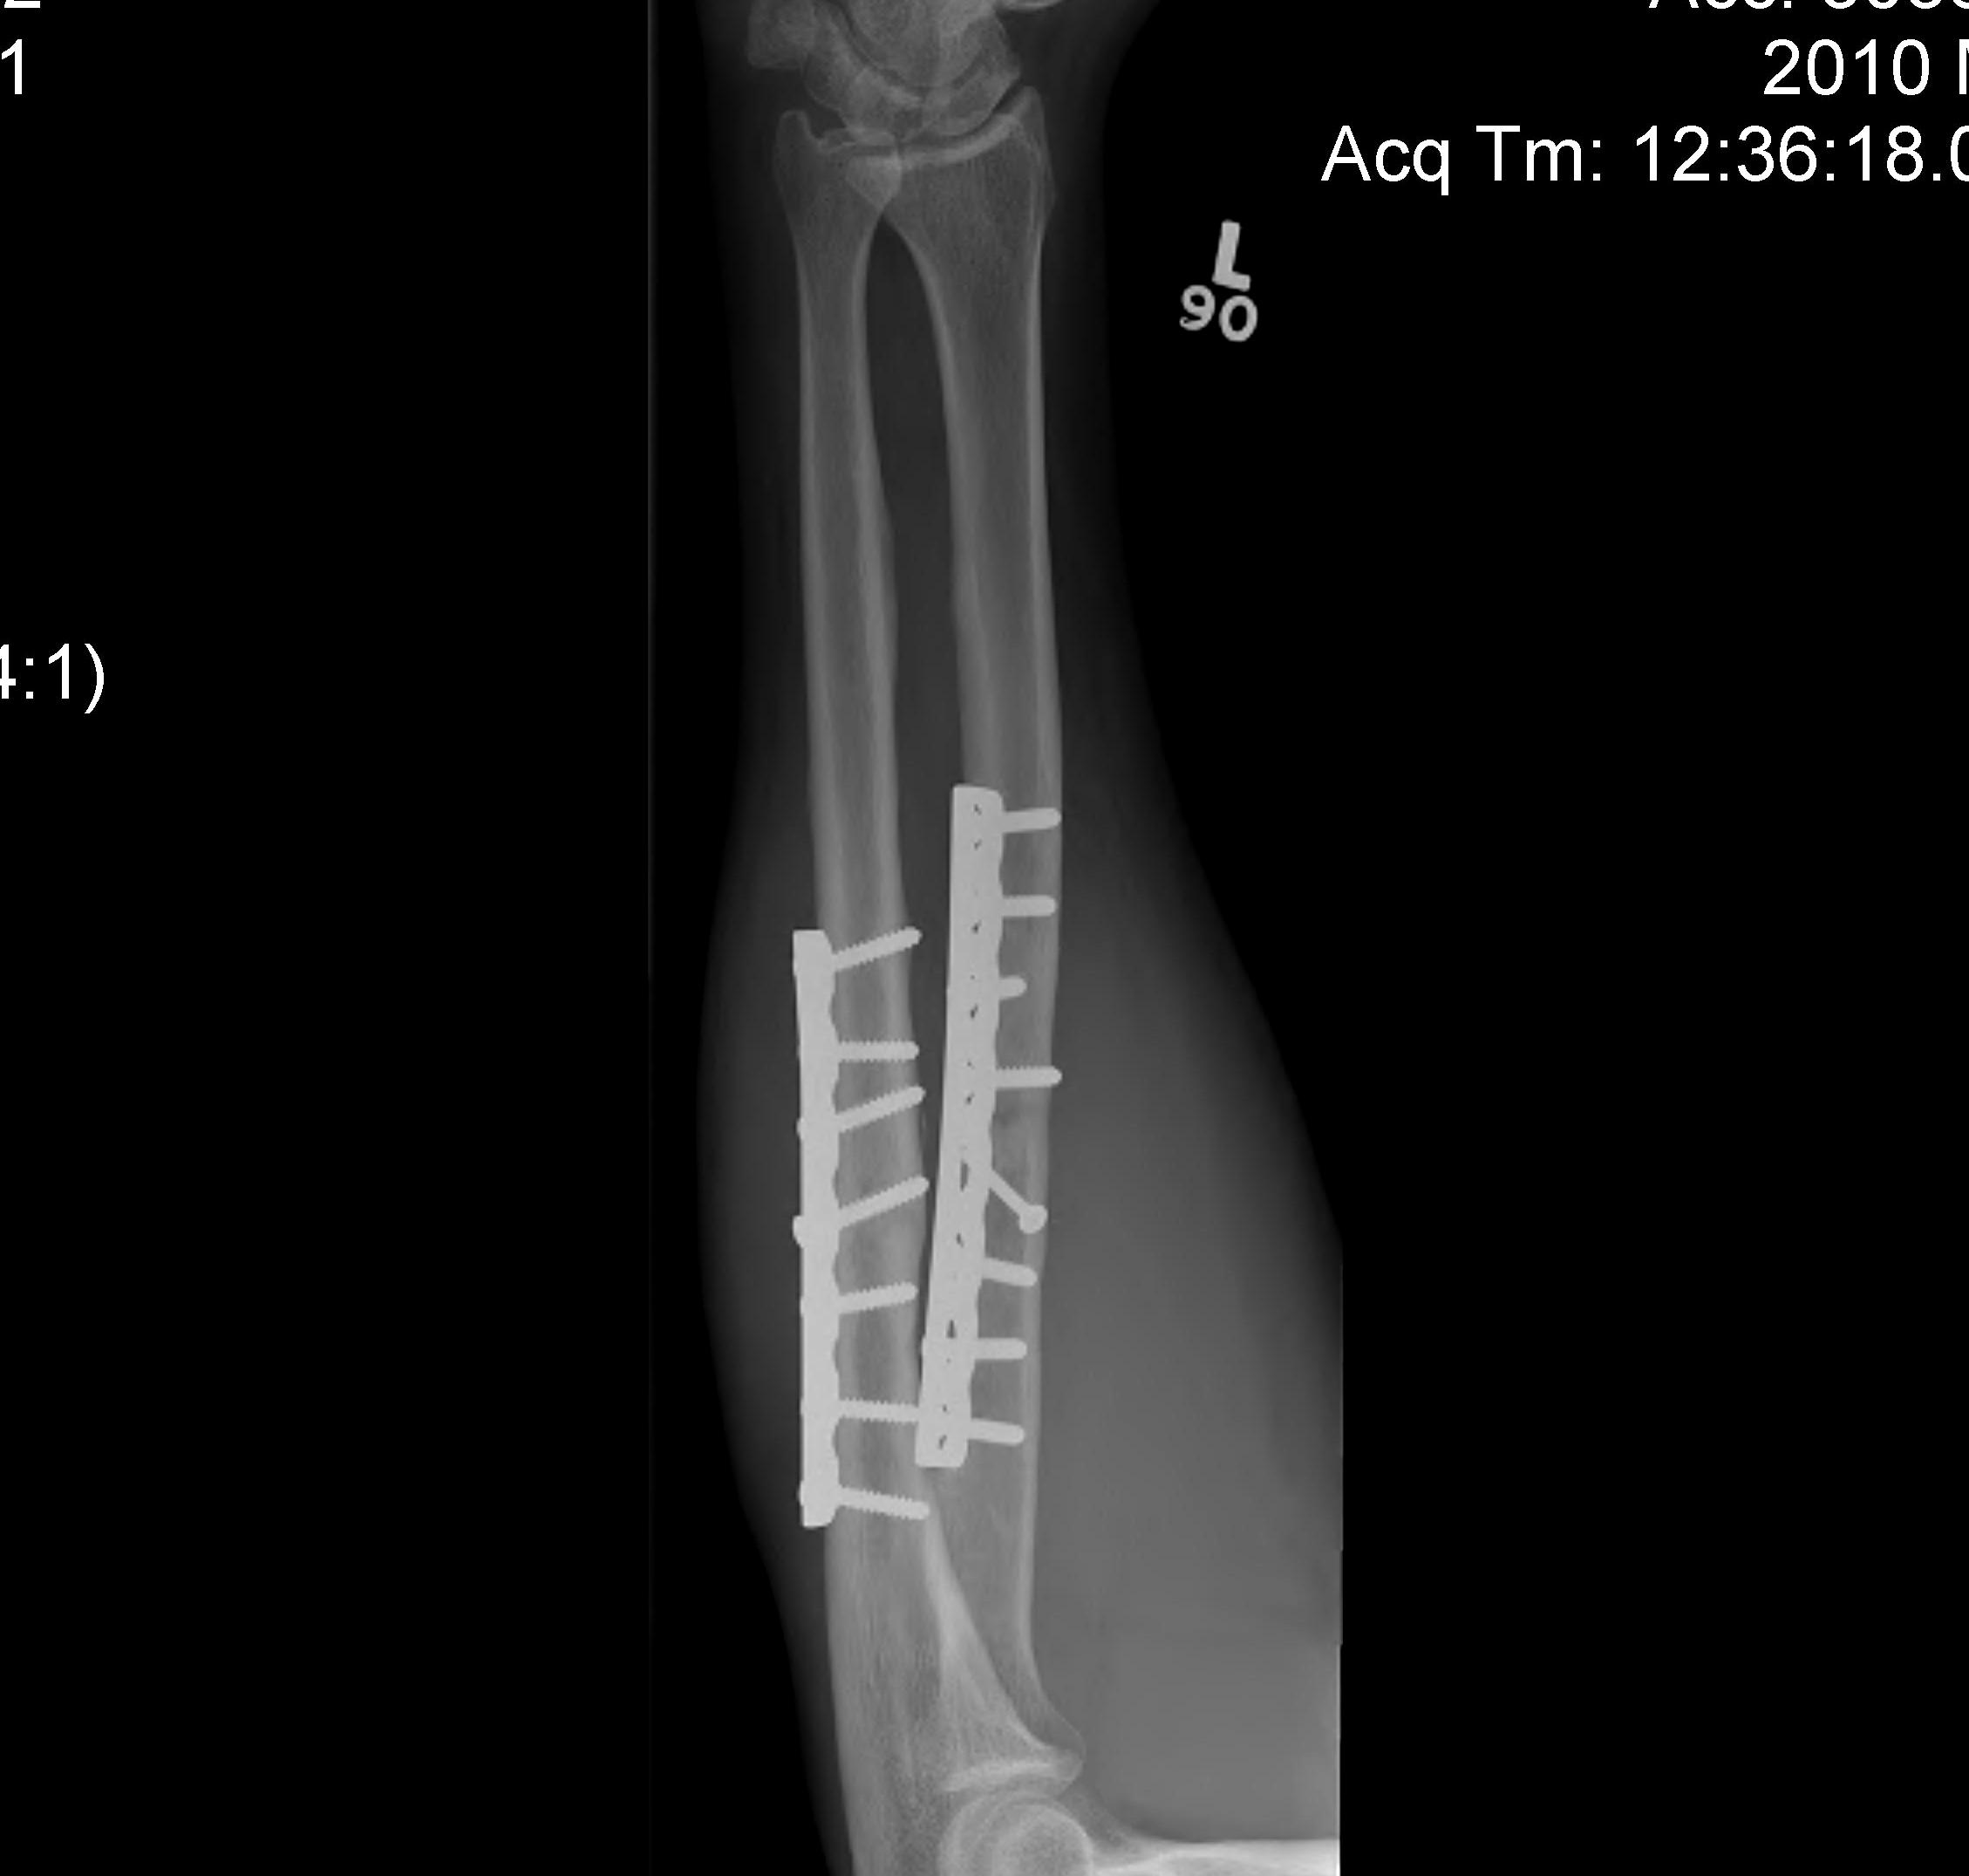

Plates

1. Neutralisation plate

2. Buttress plate

3. Tension Band plate

4. Bridging Plate

Neutralisation plate

- used to protect lag screws

- conduct part or all of the force from one fragment to another

- protect the fracture fixation from bending, shear, and rotation

- e.g. lateral malleolus fractures - lag then apply a derotation plate